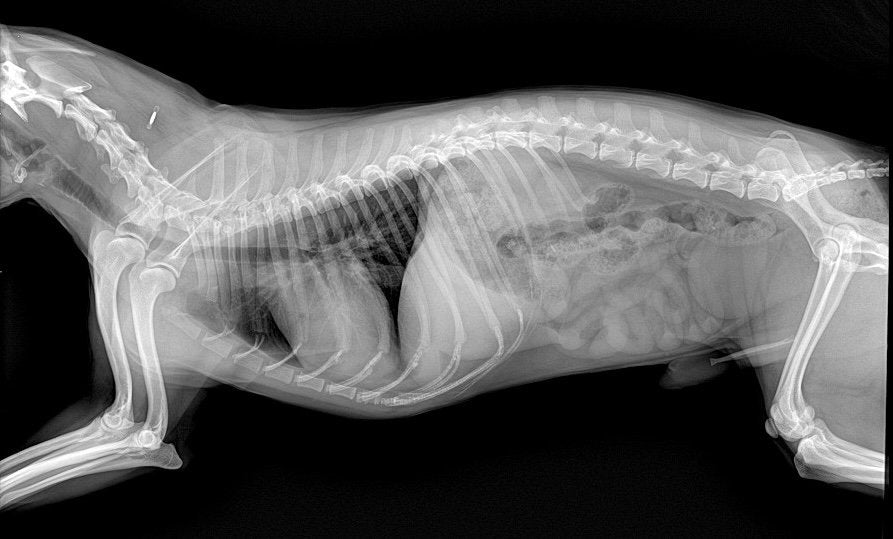

Radiology is a critical diagnostic tool in veterinary medicine, providing essential imaging for the diagnosis and treatment of animal patients. However, the use of radiological equipment involves exposure to ionizing radiation, which poses potential health risks to both animals and veterinary staff. Understanding how to implement effective radiology safety measures is essential to minimize these risks. Here are the key aspects of radiology safety in the veterinary field, focusing on principles, equipment, protective measures, and regulatory guidelines.